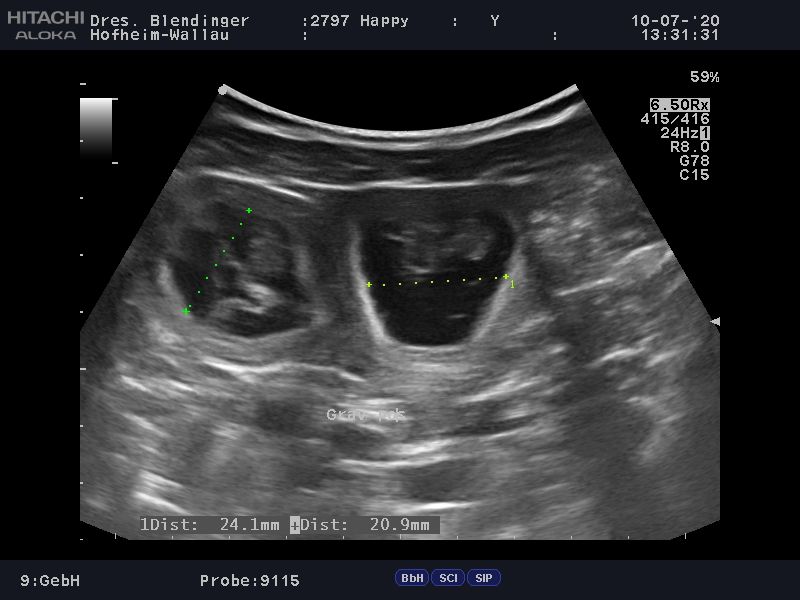

Wir haben tolle Neuigkeiten, Happy ist trächtig. Wir waren heute zum Ultraschall und laut Tierarzt, können wir uns über einen großen Wurf freuen.